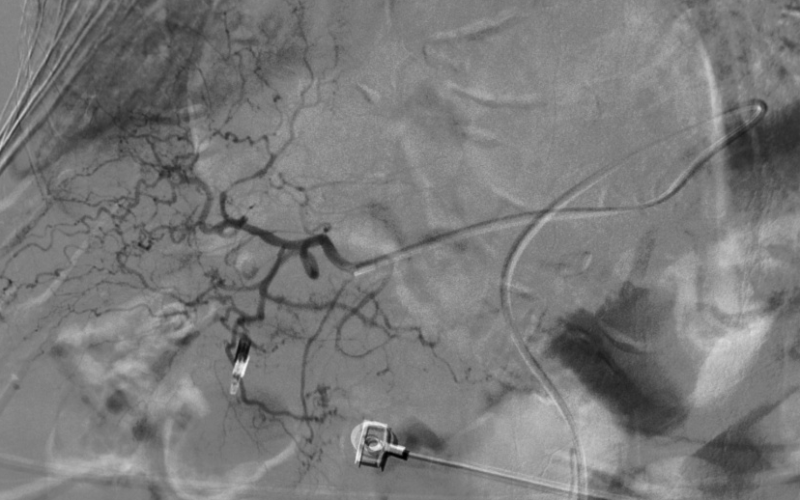

造影显示肝总动脉发出胃十二动脉及肝左右动脉。但胃十二指肠多处弯曲,微导管进入胃十二指肠动脉远端困难,更换成超细导丝后最后将微导管送入胃十二指肠动脉远端。